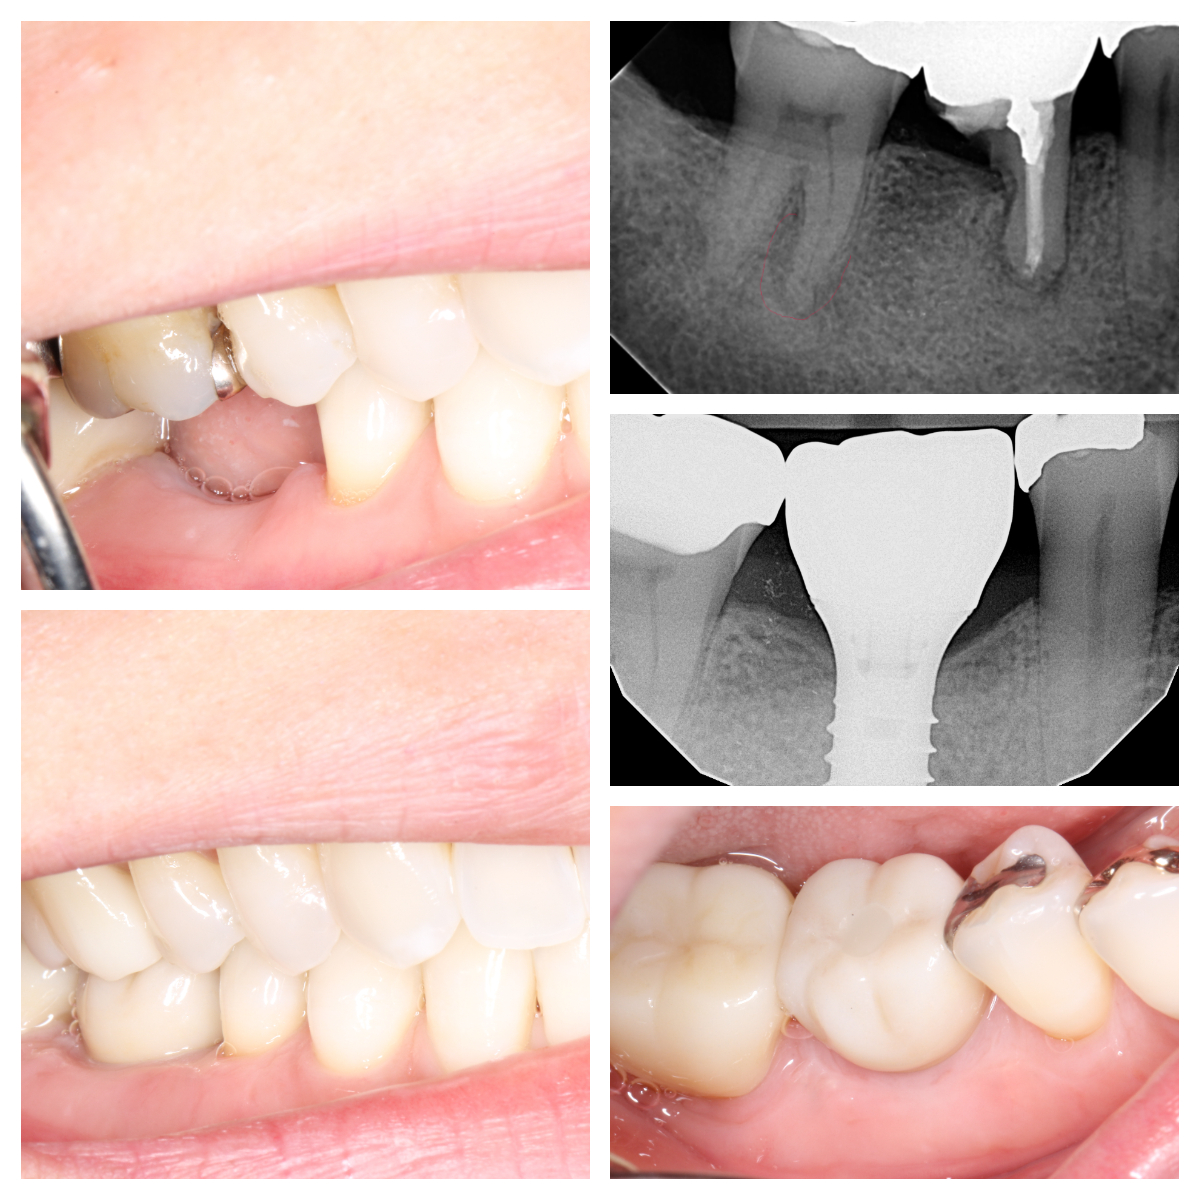

Before & Afters of Dental Implant Patients

Complete Dental Implant Cases Gallery

General Disclaimer: The results in the photographs are examples only and do not imply any certainty of the result of a procedure, and all outcomes are subject to the circumstances of the individual patient.